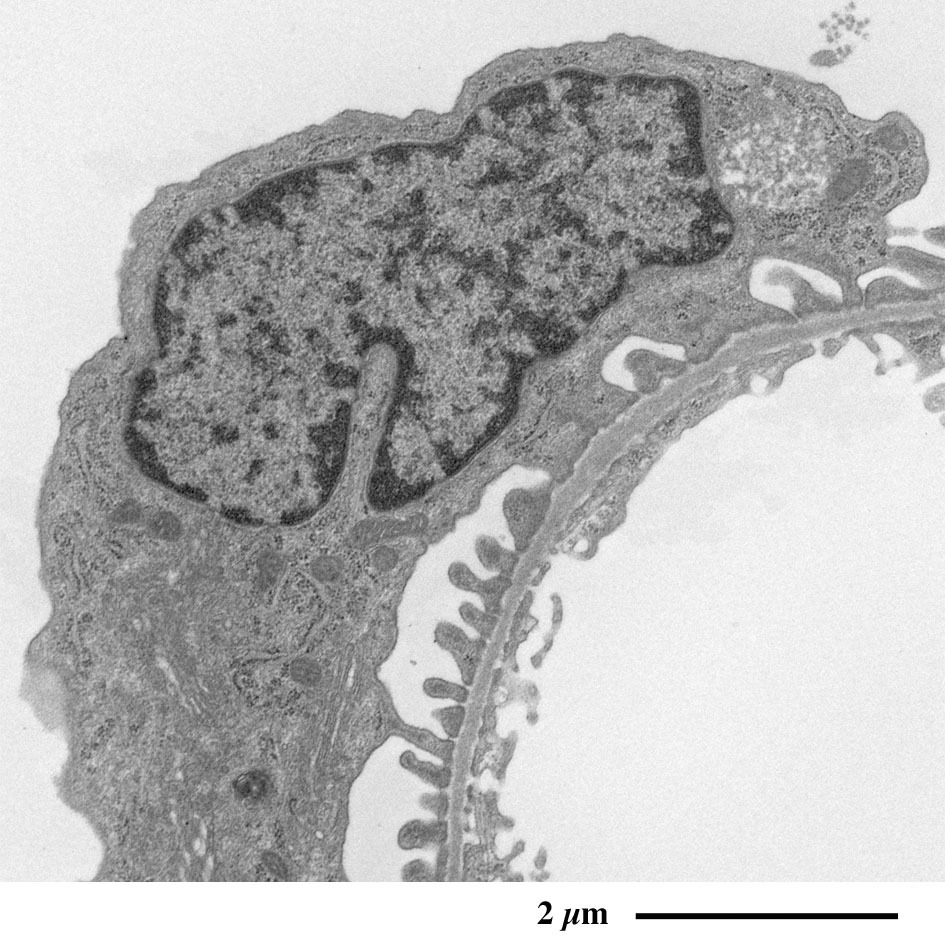

【 超薄切片の透過型電子顕微鏡画像 】

Transmission electron microscopic image of ultrathin section

糸球体の拡大像

足細胞の突起が毛細血管の外周を取り囲む様子が観察されます。